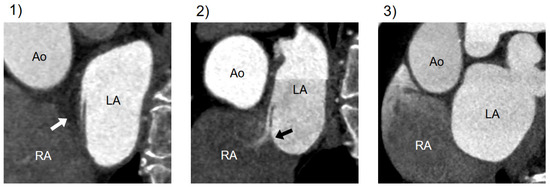

2.3. Assessment of PFO at Cardiac CT

3.4. Comparison of Diagnostic Performance of CT Findings: CLA Alone versus CLA with Jet Flow

| CLA | channel-like appearance |